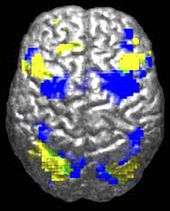

The underconnectivity theory of autism hypothesizes that autism is marked by underfunctioning high-level neural connections and synchronization, along with an excess of low-level processes.[96] Evidence for this theory has been found in functional neuroimaging studies on autistic individuals[37] and by a brainwave study that suggested that adults with ASD have local overconnectivity in the cortex and weak functional connections between the frontal lobe and the rest of the cortex.[97] Other evidence suggests the underconnectivity is mainly within each hemisphere of the cortex and that autism is a disorder of the association cortex.[98]

Research into causes has been hampered by the inability to identify biologically meaningful subgroups within the autistic population[134] and by the traditional boundaries between the disciplines of psychiatry, psychology, neurology and pediatrics.[135] Newer technologies such as fMRI and diffusion tensor imaging can help identify biologically relevant phenotypes (observable traits) that can be viewed on brain scans, to help further neurogenetic studies of autism;[136] one example is lowered activity in the fusiform face area of the brain, which is associated with impaired perception of people versus objects.[7] It has been proposed to classify autism using genetics as well as behavior.[137]